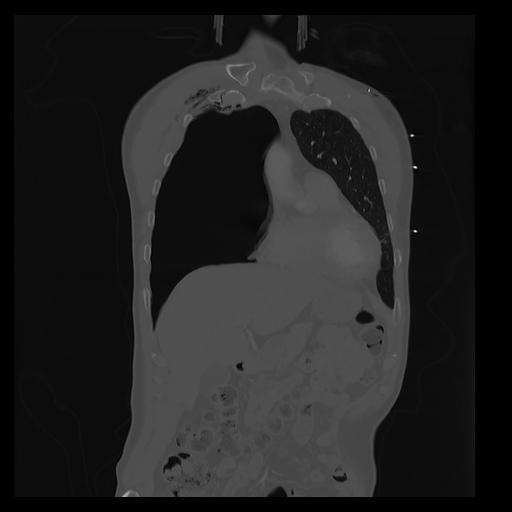

32 PULMON,CE,Coronal,3.000,PULMON,Coronal,